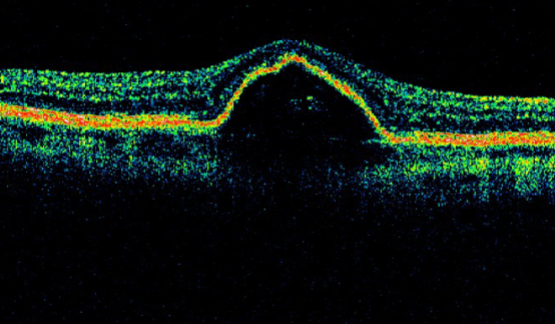

describe type 1 CNVM on OCT

describe type 2 CNVM on OCT

describe type 3 CNVM on OCT

MNV type 1

MNV type 1

MNV type 1

MNV type 1

MNV type 1

type 2 MNV

MNV type 2

MNV type 2

MNV type 2

MNV type 2

MNV type 2